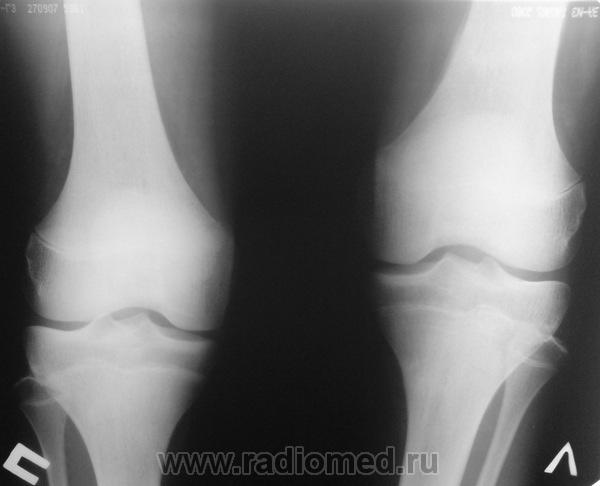

Мальчик 15 лет. Несколько месяцев назад начали беспокоить боли в коленных суставах. Травмы не было. Ребёнку был выставлен диагноз: болезнь Шлаттера, назначено лечение. На фоне лечения отмечалось значительное усиление болей, боли локализовались в левом коленном суставе. При дообследовании выявлена следующая рентгенологическая картина. Наши рентгенологи настаивают на срастающемся переломе. Но: 1) перелом без травмы? 2) бедро так не ломается

В голову приходит остеомиелит или опухоль.

Линейный периостит, уже должен был рентгенологов насторожить.

Локальный гиперостоз, выраженный болевой синдром, структура губчатого вещества диафиза не изменена наводит только на остеойд-остеому.

Я бы на первое место поставила патологическую перестройку, так называемый, стрессовый перелом. Мальчик чем-нибудь занимается?

Согласна с Ola-la - рентгенологическая картина более всего соответствует стрессорному перелому, хотя для него характерна локализация в б/берцовой кости. Меня однако, смущает и настораживает клиника - это как раз тот случай, когда я бы не дала 100% гарантии, что так не может манифестировать остеосаркома... Поскольку другие методы (МРТ, сцинтиграфия) вряд ли помогут, я бы взяла пациента на короткое ( 2недели - месяц) динамическое наблюдение.

Да, на мой взгляд, состояние после обычного "травматического перелома" (трещина), не думаю, что имел место "патологический перелом", так как костная ткань "патологически изменена" минимально. "Перистальная реакция"локальная тоже есть, на КТ "локальная  зона склероза" - все это свидетельствует именно об этом. Хотя в памяти у меня хорошо отложился Ваш последний случай о локальном утолщении кортикального слоя, когда "яйца в гнезде" еще не было. То, что анамнестически "травмы не было" - ничего не значит. Вы, по всей видимости, тоже часто встречались с такими случаями, когда ребенок не акцентировал внимание на "травме", как таковой, хотя клиника есть, боль есть. Конечно, рентгенограммы - не дай бог - ни скиалогии, ни структуры.